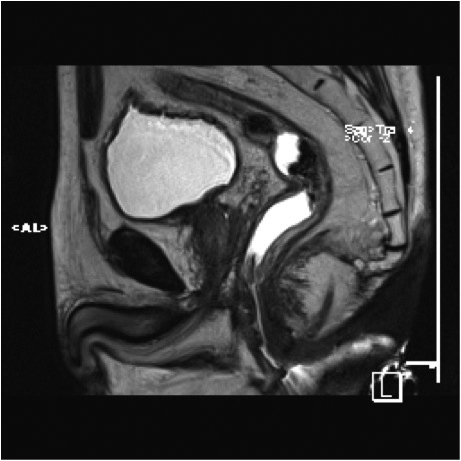

Fig.2. Același pacient post chimio-/ radioterapie – răspuns complet cu dispariția masei tumorale rectale; dispariția restricției de difuzie și reducere în dimensiuni a ganglionilor mezorectali; pacientul a beneficiat de TME şi s-a confirmat histopatologic absenţa ţesutului tumoral (pT0 pN0).

a-d) imagini T2 ponderate în 3 planuri

e) difuzie RM (b1000)

f) sagital T1 postcontrast